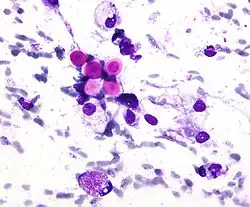

Candida

Candida species cause infections in individuals with deficient immune systems. Candida species tend to be the culprit of most fungal infections and can cause both systemic and superficial infection.[6] Th1-type cell-mediated immunity (CMI) is required for clearance of a fungal infection. Candida albicans is a kind of diploid yeast that commonly occurs among the human gut microflora. C. albicans is an opportunistic pathogen in humans. Abnormal over-growth of this fungus can occur, particularly in immunocompromised individuals.[7] C. albicans has a parasexual cycle that appears to be stimulated by environmental stress.[8]

C. auris, first described in 2009, is resistant to many frontline antifungal drugs, disinfectants, and heat, which makes it extremely difficult to eradicate. Like many fungal pathogens it mostly affects immunocompromised people; if in the blood or other organs and tissues, mortality is about 50%.[3]

Other species of Candida may be pathogenic as well, including Candida stellatoidea, C. tropicalis, C. pseudotropicalis, C. krusei, C. parapsilosis, and C. guilliermondii.[9]